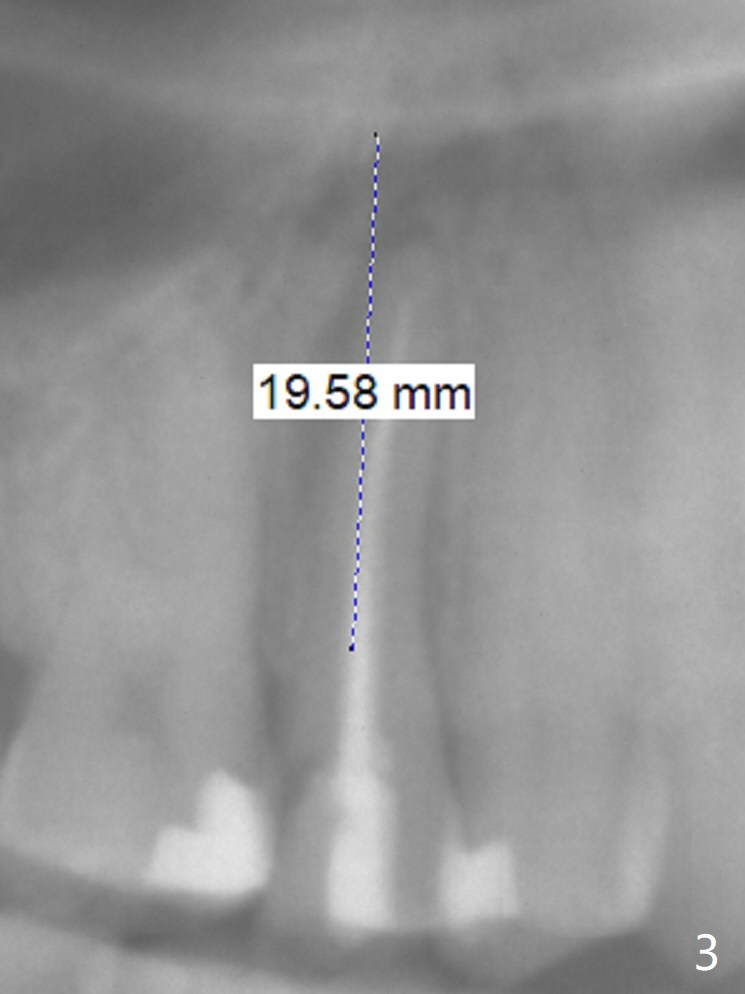

Nine months post apicoectomy of the tooth #4 of a 40-year-old man (Fig.1 <), the root has vertical fracture (Fig.2). It appears that the patient is a bruxer. Place an implant as long as 18 mm (bone level, Fig.3). Start osteotomy in the middle of socket, since there is bone resorption both buccally (apicoectomy) and palately (Fig.4 *). The implant should occupy the meisodistal space for primary stability. Measure root dimension post extraction to determine the implant diameter. Use a 3.8 mm dummy implant.